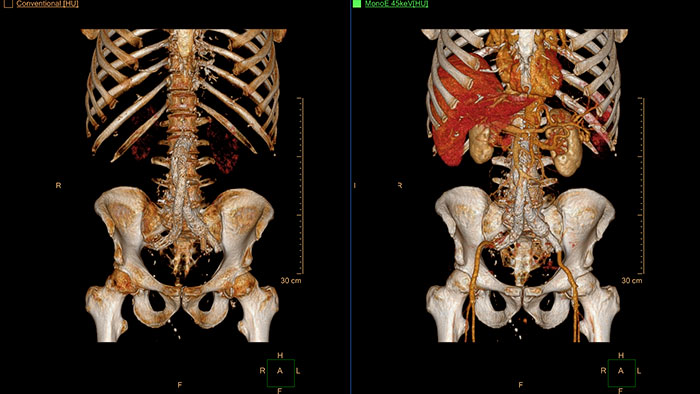

Spectral Tumor Tracking

CT Spectral Tumor Tracking

Inspection of tumors, as contrast enhanced, soft tissue oriented, and whole-body scans

Assists clinicians in viewing and evaluating CT images acquired on the IQon CT scanner for the inspection of tumors, as contrast enhanced, soft tissue oriented, and whole-body scans.

It supports lesion viewing and analysis based on different spectral data types such as iodine density maps or virtual non-contrast-enhanced images.

Benefits

• Tissue segmentation and editing tools allow to generate user-defined ROI and the application provides information on physical (length, width, volume) and composition properties (effective atomic number, attenuation, HU) of the tumor.

• The application supports longitudinal viewing of cases taken from different examination times.